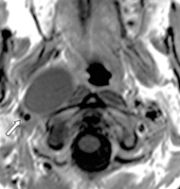

| 04:56, 23 October 2018 | Paramass mri.jpg (file) |  |

52 KB | Drtbalu | |